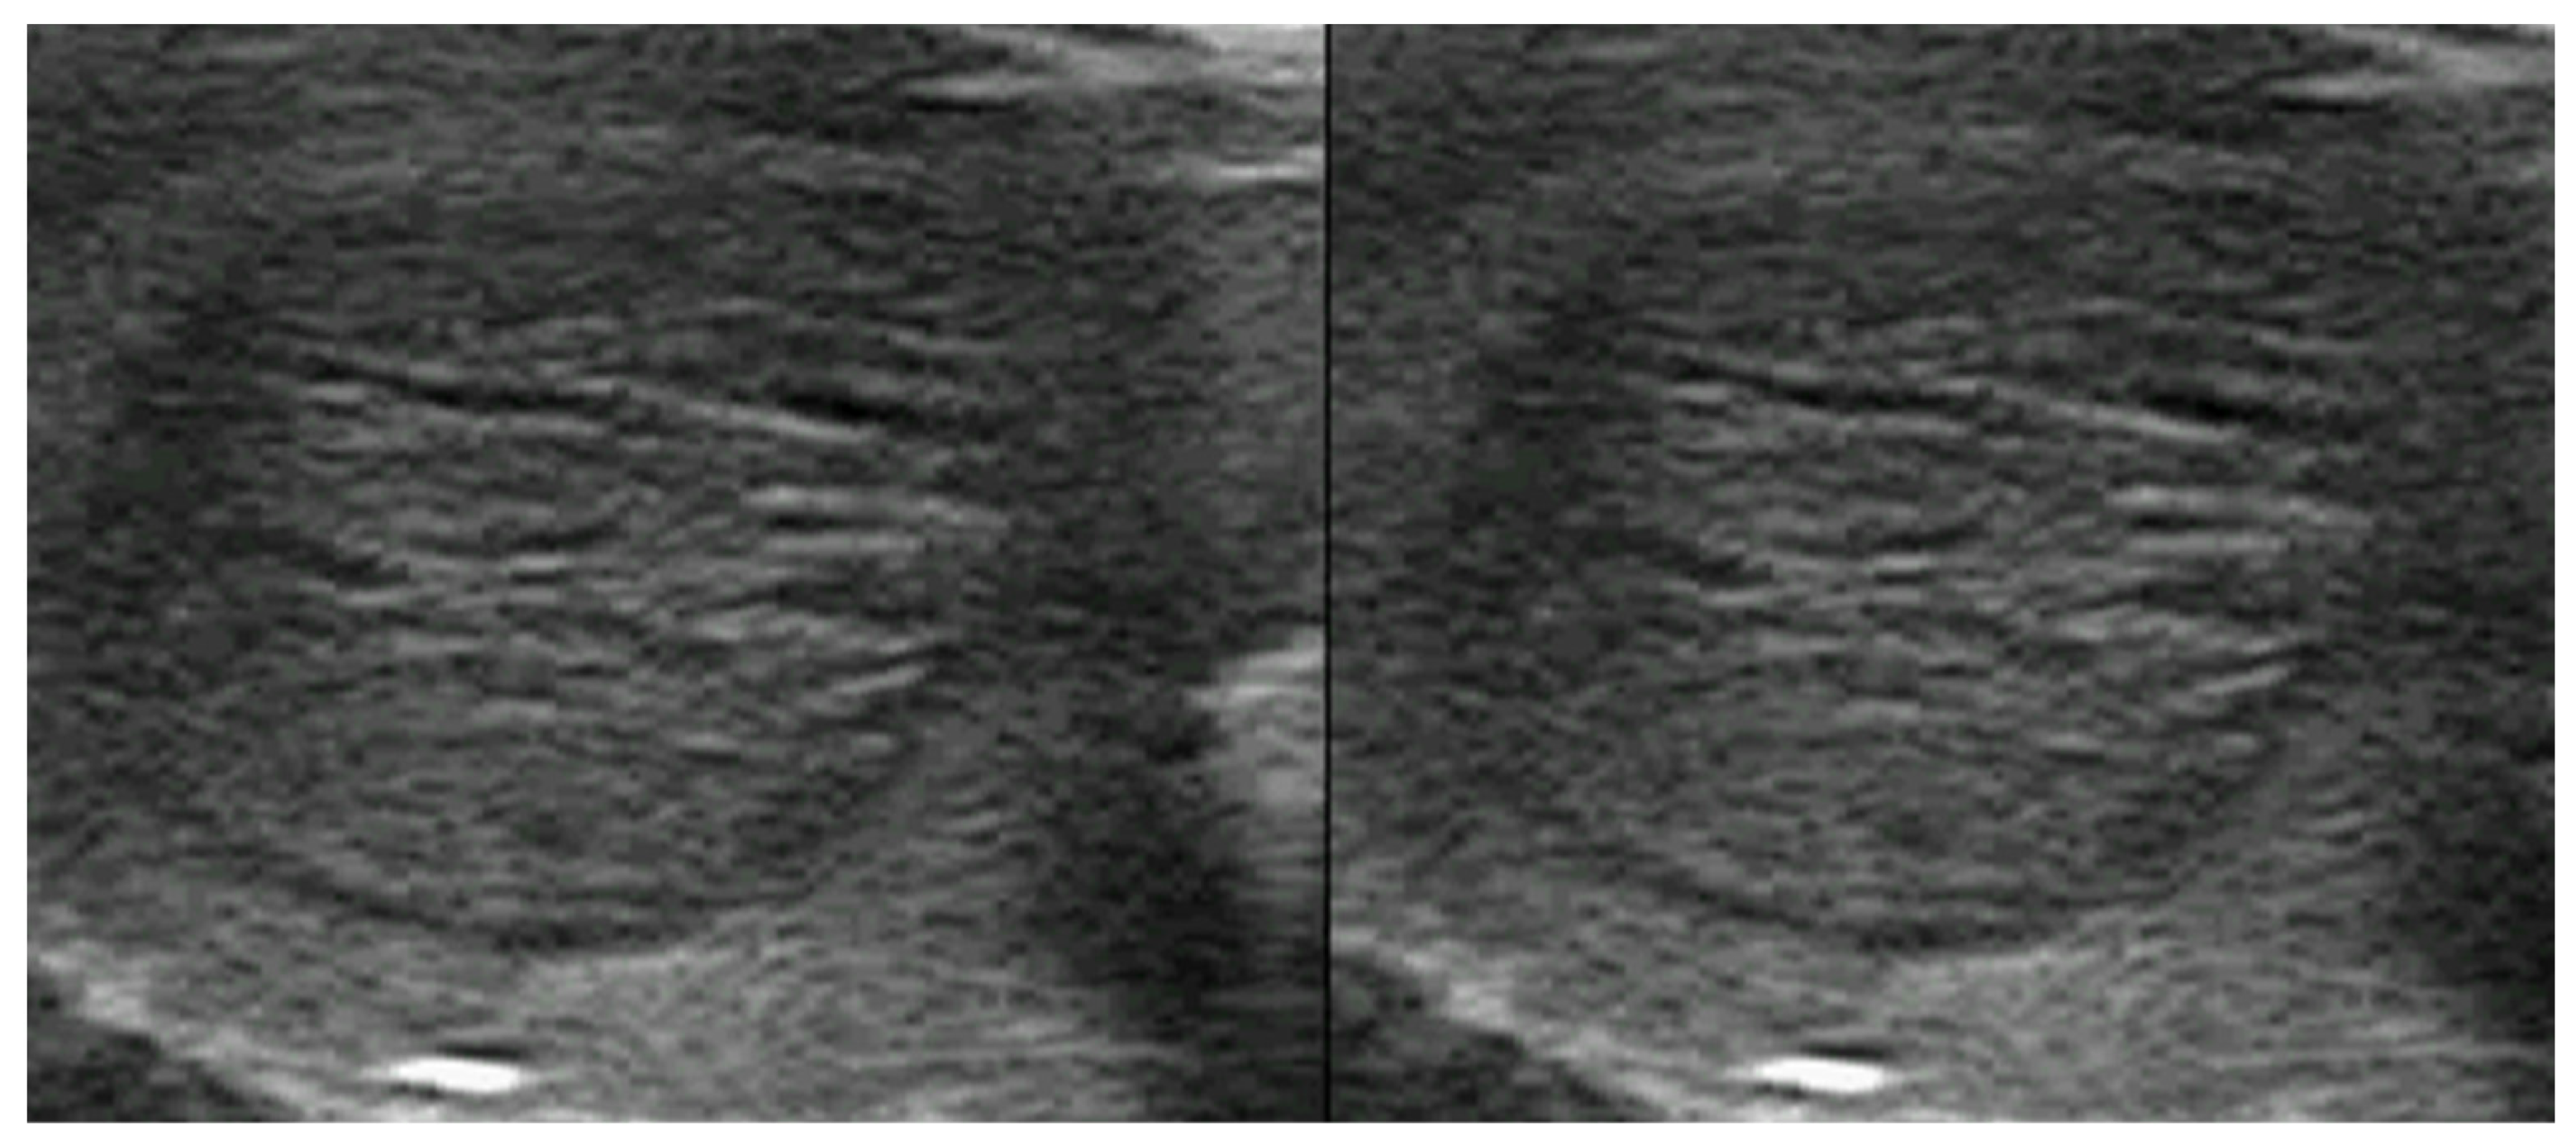

3.2. Hypothyroidism